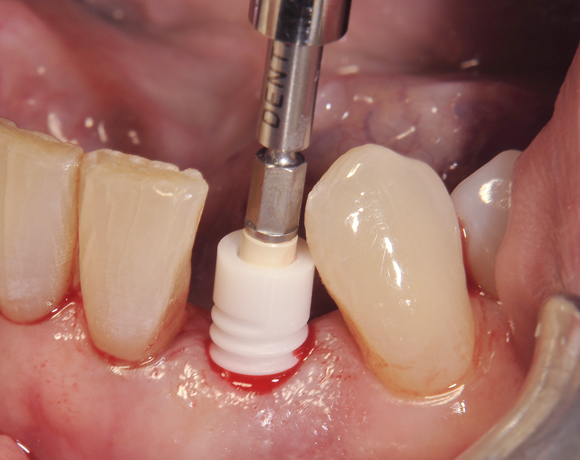

Am Beispiel dieses Patientenfalls wird gezeigt wie ein Einzelimplantat für den Unterkieferfrontzahn 33 eingesetzt wird.